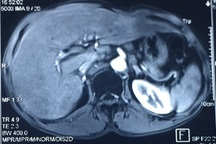

Bệnh nhân nam 63 tuổi (tiền sử mổ mở cắt lách do chấn thương bụng) vào bệnh viện khám vì nuốt vướng. Bệnh nhân được nội soi thực quản - dạ dày, chụp cắt lớp vi tính Ngực - Bụng và làm các xét nghiệm khác. Kết quả cho thấy bệnh nhân bị ung thư thực quản 1/3 giữa giai đoạn cT2N0M0.

Một số hình ảnh của ca phẫu thuật